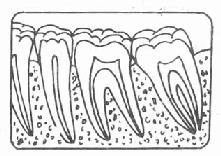

牙周袋形成:由于炎症的扩展,牙周膜被破坏,牙槽骨逐渐吸收,牙龈与牙根分离,使龈沟加深而形成牙周袋。可用探针测牙周袋深度。X线检查时可发现牙槽骨有不同程度的吸收。如图3-7~11.

| 图3-7 正常牙槽骨 | 图3-8 牙槽骨Ⅰ度吸收 |